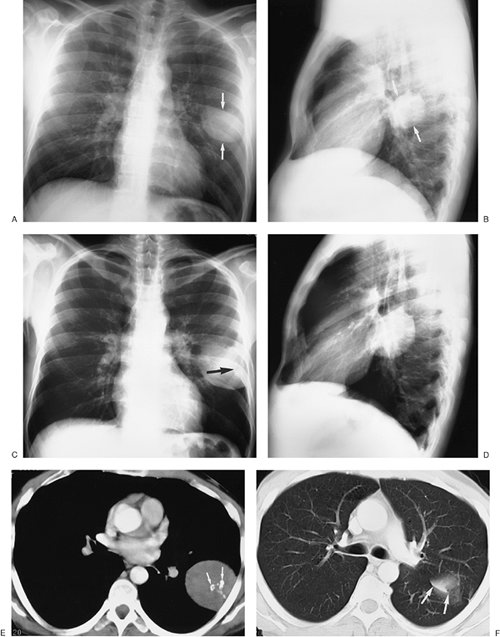

FIGURE 9-27. Benign localized fibrous tumor of the pleura. A: PA chest radiograph of a 32-year-old asymptomatic woman shows a well-circumscribed round mass in the left middle lung (arrows). B: Lateral view shows that the mass is positioned adjacent to the left major fissure (arrows). C: PA chest radiograph obtained 4 years later shows that the mass has increased in size. Faint calcification is now visible within the mass (arrow). D: Lateral view obtained at the same time as (C). E: CT shows that the mass is homogeneous, abuts the lateral pleural surface, and has coarse calcifications (arrows). F: CT with lung windowing shows that the top of the tumor abuts the major fissure (arrows).